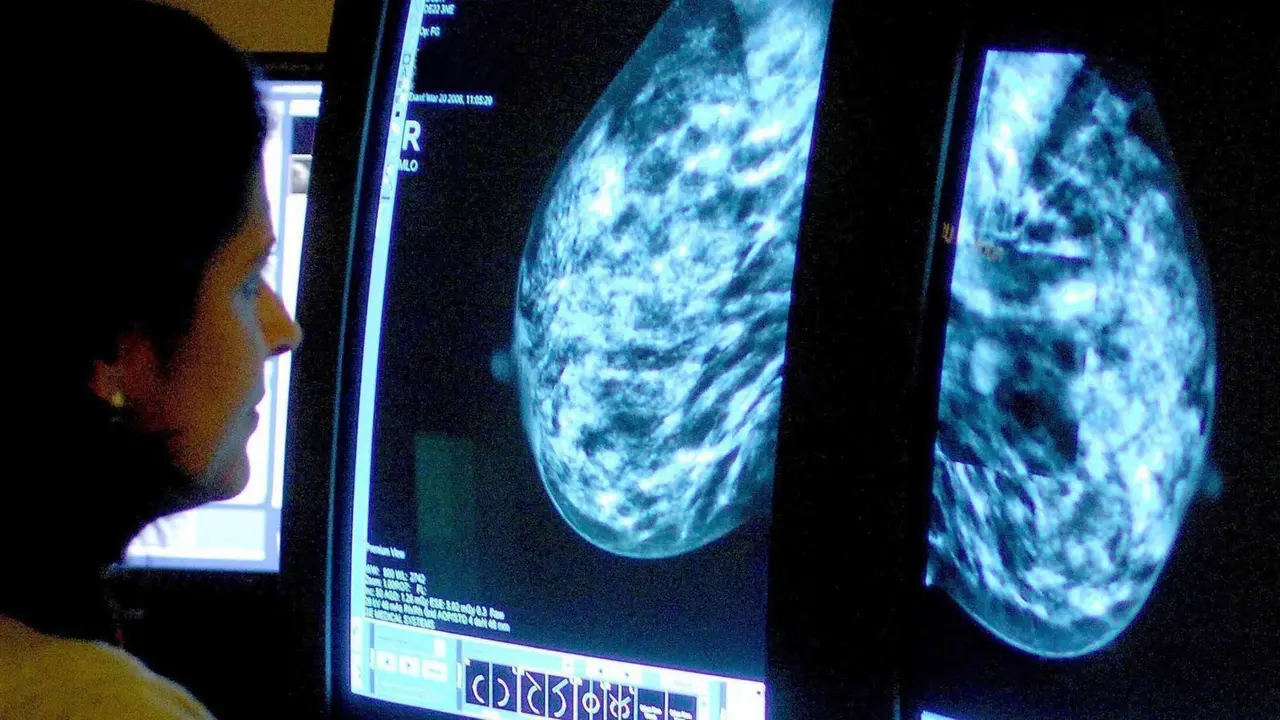

AI-assisted mammograms cut risk of developing aggressive breast cancer

Interval cancers are aggressive tumours that grow during the interval after someone has been screened for cancer and before they are screened again, and AI seems to be able to identify them at an early stage People who are screened for breast cancer by AI-supported radiologists are less likely to develop aggressive cancers before their next screening round than those who are screened by radiologists alone, raising hopes that AI-assisted screening could save lives. "This is the first randomised controlled trial on the use of AI in mammography screening," says Kristina LÃ¥ng at Lund University in Sweden. The AI-supported approach involves using the software - which has been trained on more than 200,000 mammography scans from 10 countries - to rank the likelihood of cancer being present in mammograms on a scale of 1 to 10, based on visual patterns in the scans. The scans receiving a score of 1 to 9 are then assessed by one experienced radiologist, while scans receiving a score of 10 - indicating cancer is most likely to be present - are assessed by two experienced radiologists. An earlier study found that this approach could detect 29 per cent more cancers than standard screening, where each mammogram is assessed by two radiologists, without increasing the rate of false detections - where a growth is flagged but follow-up tests reveal it isn't actually there or wouldn't go on to cause problems. "That was terrific," says Fiona Gilbert at the University of Cambridge, who wasn't involved in the trial. Now, LÃ¥ng and her colleagues have found that the AI approach also reduces the likelihood of people developing so-called interval cancers. These are tumours that develop rapidly in the time interval between screenings - hence the name - and that consequently tend to be particularly aggressive and more likely to spread elsewhere in the body. LÃ¥ng and her colleagues made the discovery during an analysis of more than 100,000 women in Sweden, aged 55 on average. They randomly assigned about half of the women to receive their standard round of breast cancer screening, where each mammogram is assessed by two radiologists. The remaining participants were screened initially by the AI model - which was developed by biotech firm ScreenPoint Medical in Nijmegen, the Netherlands - and then the scans were assessed by radiologists, most of whom had at least five years of experience in analysing mammograms. The women who received the AI-assisted screening were 12 per cent less likely, on average, to develop an interval cancer than the women who received the standard screening. "When we got the results, we were extremely thrilled," says LÃ¥ng. This result may be down to the fact that the AI is better able to detect cancers at a very early stage. So while radiologists might overlook small tumours that would develop into an interval cancer, the AI can spot them. Even so, the study was only designed to explore whether AI can work as well as standard screening, not to see if it can perform better, meaning further trials are needed to confirm it really is superior, says LÃ¥ng. What's more, the team didn't assess whether the AI-supported approach performs better in certain ethnic groups. Further trials, including an ongoing trial in the UK, will help to address this, says Gilbert. Research should also be conducted to test whether less experienced radiologists see the same benefit when using AI, but Gilbert doesn't expect a huge difference. Off the back of these results, LÃ¥ng expects the AI approach to be rolled out across south-west Sweden, where the trial was performed, within a few months. But it will probably take about five years for other countries to complete similar trials that justify the roll-out elsewhere, says Gilbert. "Countries need to see what the impact is on their own population, where people are screened more or less often, and are of different ethnicities," she says. They also need to establish whether the AI approach is cost-effective. By some estimates, AI assistance may be worth investing in if it cuts interval cancer rates by at least 5 per cent. Radiologists will also need to be trained, although that probably won't be too cumbersome as the software is fairly easy to use, says LÃ¥ng. It's important to note that, even as AI improves, breast screening should always involve radiologists, says LÃ¥ng. "Women that participate in screening say they do not want to have AI as a standalone tool, they want to have a human in the loop, and I agree with them. I think it's very important that it's a tool for radiologists," she says.